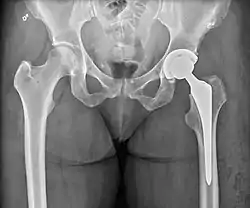

استبدال مفصل الورك (بالإنجليزية: Hip replacement) هي عملية جراحية يتم خلالها استبدال الورك الطبيعي بجهاز مفصلي اصطناعي للسماح للمريض بالمشي وأداء مهماته بشكل طبيعي تقريبا. يمكن أن تجرى عملية استبدال مفصل الورك بشكل نصفي أو كلي.[1][2][3] يتم اللجوء إلى هذا الإجراء بشكل عام بغرض التخلص من ألم التهاب المفصل أو لإصلاح تخرب المفصل الفيزيائي كجزء من علاج كسر مفصل الورك. يتألف استبدال مفصل الورك الكلي (رأب مفصل الورك الكلي) من استبدال كل من تجويف الحُق و رأس الفخذ معا، في حين يتم خلال عملية استبدال مفصل الورك النصفي (رأب المفصل النصفي) اللجوء لاستبدال رأس الفخذ فقط . تعتبر عملية استبدال مفصل الورك حالياً واحدة من عمليات جراحة العظام الأكثر نجاحاً وموثوقيةً، حيث أظهر 97 في المائة من المرضى الذين خضعوا للعملية تحسناً ملحوظاً. تشير معظم التقديرات إلى أن ما يقرب من 58 في المائة من إجمالي عمليات استبدال مفصل الورك تظل صالحة إلى غاية 25 عاما بعد العملية.[4] حسب إحصائيات لسنة 2012، فإن عملية استبدال مفصل الورك تكلف في المتوسط ما قيمته 40364 دولار أمريكي في الولايات المتحدة، وحوالي 7700 إلى 12000 دولار أمريكي في معظم الدول الأوروبية.[5]

![]() صورة بالأشعة السينية تظهر الورك الأيسر (يمين الصورة) الذي تم استبداله بآخر اصطناعي. صورة بالأشعة السينية تظهر الورك الأيسر (يمين الصورة) الذي تم استبداله بآخر اصطناعي. | |

يتم بعد الجراحة، إجراء تصوير الشعاعي لمنطقة المفصل المزروع وذلك للتأكد من نجاح العملية وضمان التكوين المناسب للأطراف الاصطناعية للورك. يؤثر اتجاه تجويف الحق المزروع على نطاق حركة الساق، كما يعد أيضا عاملا محددا لإمكانية حدوث خطر الخلع من عدمه.[31] لهذا الغرض، يتم اللجوء لإجراء قياسات خاصة لمقارنتها بالقيم الطبيعية. من بين أهم هذه القياسات نجد مثلا ميلان الحق ودرجة إنقلابه إلى الأمام بالنسبة للمستوى الإكليلي والمستوى السهمي على التوالي.